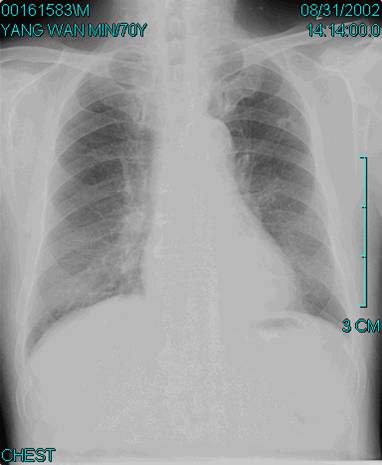

照片名称:正常胸片